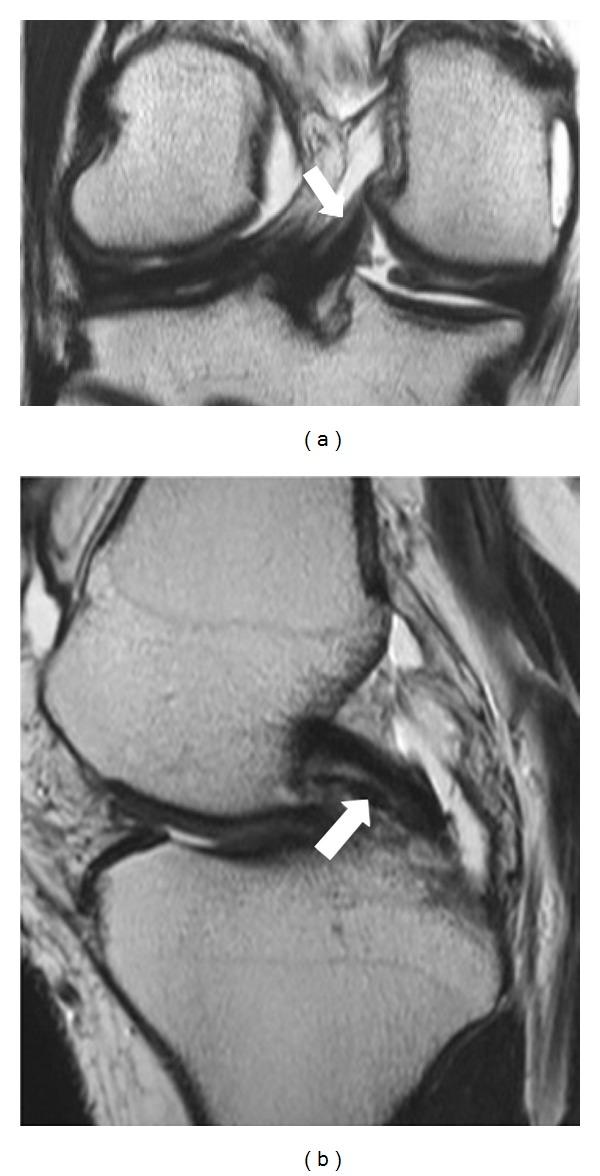

前后半月板股骨韧带:磁共振成像评估

Anterior and posterior meniscofemoral ligaments: MRI evaluation.

Although meniscofemoral ligaments are distinct anatomic units, their anatomy and function are controversial from an anatomic and radiologic point of view. Five hundred knee MR examinations were retrospectively studied in an effort to demonstrate the incidence and variations regarding sex and age distribution, as well as the anatomy of the meniscofemoral ligament at magnetic resonance imaging. Patients were mostly men, three hundred and twelve, in contrast with women who were fewer, one hundred eighty-eight patients. The mean age of the patients who were included in this study was 46 years. More than half of them were between 20 and 40 years old; one hundred thirty-three patients among 20 to 30 years old and one hundred and one patients among 31 and 40 years old, in total two hundred thirty-four patients.

虽然半月板股骨韧带是独特的解剖结构,但从解剖学和放射学角度来看,它们的解剖结构和功能仍存在争议。我们回顾性研究了500例膝关节磁共振成像(MR)检查,以阐明半月板股骨韧带在性别、年龄分布方面的发生率和变异情况,以及其在磁共振成像中的解剖结构。患者以男性居多,共312例,女性较少,为188例。纳入本研究的患者平均年龄为46岁。其中一半以上患者年龄在20至40岁之间;20至30岁的患者有133例,31至40岁的患者有101例,总计234例。